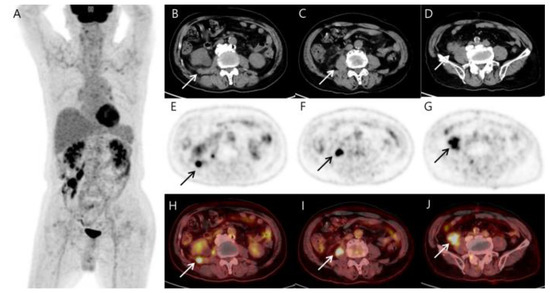

Figure 2.

MIP (A), CT (B–D), PET (E–G), and fusion PET/CT (H–J) of the 18F-FDG PET/CT images reveal several hypermetabolic soft tissue nodules (arrows) involving the terminal ileum (SUVmax 17.87), right psoas muscle (SUVmax 14.87), and reptroperitoneum (SUVmax 12.22). The terminal ileal mass shows a comet-tail-like pattern of increasing absorption toward the back, suggesting invasion into the psoas muscle. Other than the above-described area, no significant abnormal findings in other parts of the body are included in the image. As shown in the MIP image, it differs too much from the typical prostate cancer metastasis that spreads from bottom to top along lymph nodes to be considered prostate cancer metastasis. Additionally, it is not appropriate to consider it a small intestinal adenocarcinoma and metastasis because the patient has no symptoms. The patient had previously been treated for lymphoma, and based on the 18F-FDG PET/CT findings, we first considered the possibility of recurrent lymphoma or sarcoma.